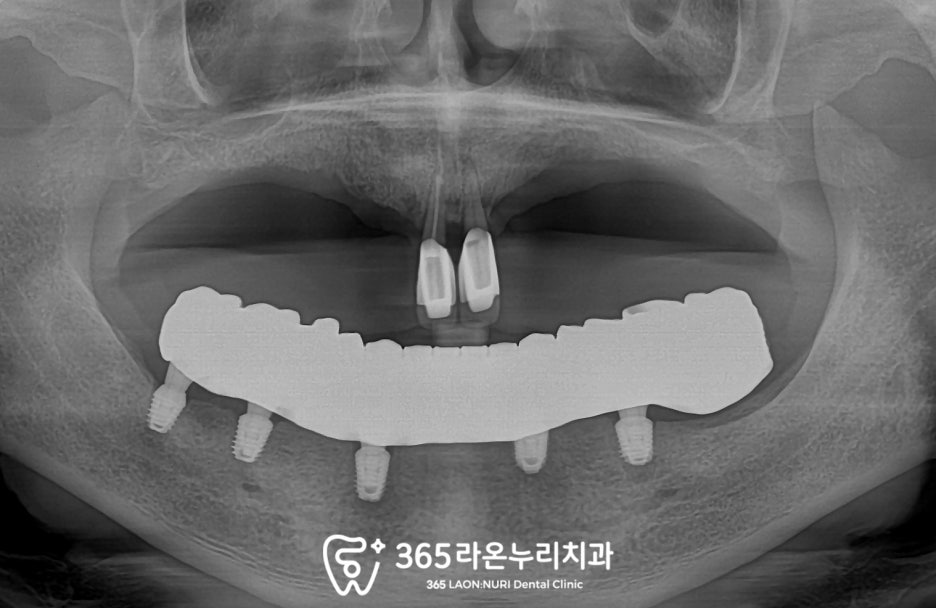

그래서 보이시는 것처럼

추가적으로 몇 개를 더 심었는데요,

기존 세 개를 포함하여 단 2개만 더 심었기에

비용 부담도 많지 않도록 해드렸습니다.

본래 치아 개수가

16개(사랑니 포함)인 것을 생각해 보면

5개만으로 저작기능을 대체할 수 있다는 게

정말 큰 장점이죠?

6개월 정도 모든 진료를 마치고

어버트먼트를 체결한 뒤

최종 보철을 올려드린 모습입니다.

상악의 덴처와도 적절한 교합관계를 이룰 수 있도록

섬세하게 조정해 드렸으며

이전의 들썩거리고 단추 형식이 아닌

나사로 연결되는 방식이기에

훨씬 더 편안하실 겁니다.